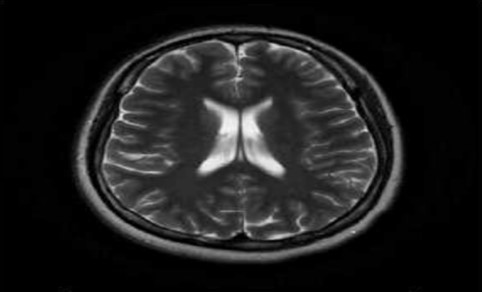

Deep learning-based image classification of MRI brain image

This article reviews the latest research on MRI brain image classification techniques based on deep learning. Firstly, MRI brain image classification and traditional machine learning methods applied to MRI image classification were briefly introduced. Then, a review was conducted on existing MRI brain image classification methods based on deep learning. The article reviews past and recent related research and provides a detailed introduction to the application of deep learning methods in MRI brain image classification. This includes some traditional machine learning methods and research achievements in deep neural networks (DNN), convolutional neural networks (CNN), and transfer learning. The most commonly used deep learning architecture for image classification is CNN. Research has shown that deep learning methods have high accuracy and performance in MRI brain image classification and can automatically extract image features for effective classification. Therefore, deep learning methods provide doctors with more comprehensive information, help them make more accurate diagnoses and formulate treatment plans, and have broad prospects for application in MRI brain image classification. In the future, the further development of deep learning technology will achieve better auxiliary effects on diagnosis, treatment, and scientific research related to the brain.